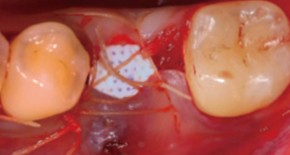

3. SuturePain and swelling can be minimized and quick return to daily life is possible.

2. Suture after MagiCore placement

3. Recovery